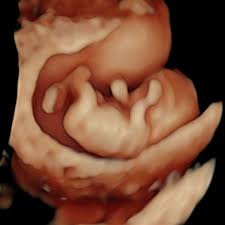

Dr Nabielek Ultraschallbilder 3d Ultraschall

Dr Nabielek Ultraschallbilder 3d Ultraschall from le-cdn.website-editor.net